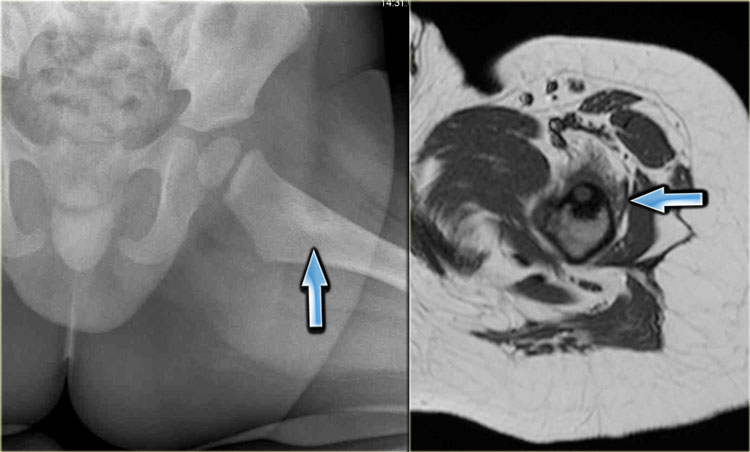

CT image of lytic lesion with central mineralisation in the right acetabulum.

T2-weighted coronal MR image shows abundant osseous edema surrounding the lesion: osteoblastoma.

The differential diagnosis includes a chondroblastoma.